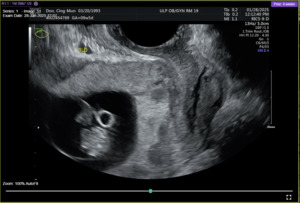

On admission for planned D&C, consents for laminaria placement, suction dilation and curettage under ultrasound guidance, possible uterine artery embolization, and possible hysterectomy were discussed and signed. The patient then underwent successful placement of a large and a medium-sized laminaria without complication. She subsequently underwent suction D&C with ultrasound guidance (Figure 3). Despite the prophylactic placement of 400 micrograms of rectal misoprostol and the administration of 20 units of Pitocin in IV fluids at the start of the case, the patient experienced significant hemorrhage during the procedure with an estimated blood loss of 1500 mL. Intraoperative findings raised concern for uterine rupture (Figure 4). A Foley balloon inflated with 30cc of saline was placed for attempted intrauterine tamponade (Figure 5), and a brisk blood loss of 500 mL immediately filled the foley catheter bag. Vaginal packing and intramuscular methergine were given as additional attempts to control the bleeding, but the patient’s hemodynamic status rapidly deteriorated. This necessitated volume resuscitation and transfusion of two units of packed red blood cells. An emergent exploratory laparotomy was then performed to identify the source of the bleeding with preparedness to repair any defects or perform a hysterectomy to prevent exsanguination. A thorough survey of the uterus, adnexa, and adjacent pelvic structures revealed no overt source of bleeding, uterine rupture, or organ invasion. The uterine and bladder serosa were intact. No hemoperitoneum was found. Further inspection revealed no additional blood loss beyond the 500 mL noted in the foley bag. Blood loss was ppropriately corrected for, and the patient became hemodynamically stable. The abdomen was closed, and the patient was transferred to interventional radiology for uterine artery embolization, prevented additional bloodloss. Following embolization, the patient was noted to be stable and extubated without issue.